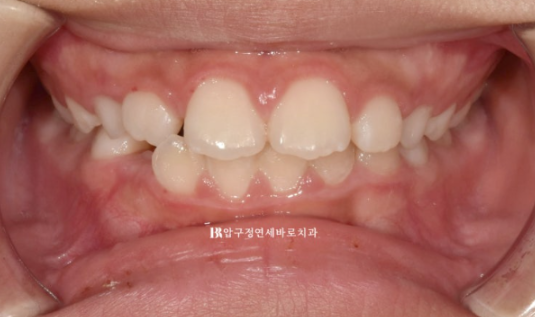

24년 4월까지 6개월간 장치를 낀 후 모습입니다.

24.04

중심선은 잘 맞고

영구치들이 잘 내려오고 있습니다.

앞니 뻗친 부분도 개선이 되었습니다.

그러나 여전히 아래 앞니 배열이 약간 틀어진 부분이 있고 위 앞니 돌출을 좀 더 해결하기 위해 추가장치 제작에 들어갑니다.

24.12

다행히 한달만에 배열이 잡히고 중심선은 잘 맞으며 측절치도 잘 내려왔습니다.

교합이 좋지 않으면 교정을 마무리 짓지 않습니다.

어린이 교정이지만 결과가 성인교정 결과에 준하는 만큼 철사 유지장치도 성인교정에 준하게 들어갑니다.

교정 종료 시점 유치는 아직 3개가 남았습니다.

전 후 비교 보겠습니다.

치료 기간은 1년 2개월입니다.

23.10~24.12

뻗쳐있던 앞니 각도가 개선이 되면서 돌출이 해소가 되었습니다.